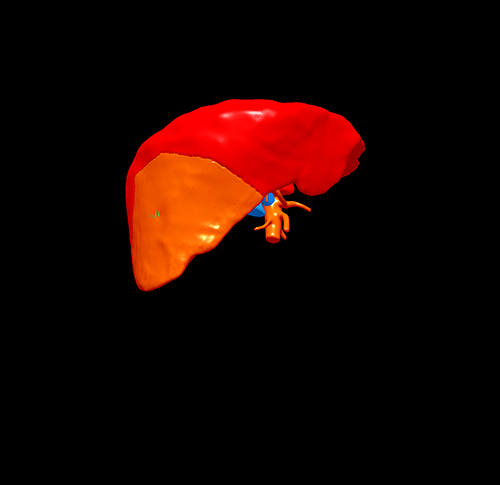

S6肝癌 胆囊结石--腹腔镜右肝部分切除 胆囊切除